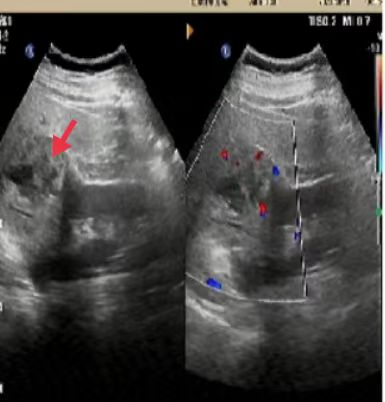

05、**男士,58岁

于2023年10月17日在宜昌仁康体检部体检,腹部彩超检查提示:肝肾之间9.0*6.3cm混合回声团。2023年10月18日通知客户到三甲医院进一步检查。2023年11月19日跟踪回访,客户反馈已在当地某三甲医院完成肿瘤切除手术。